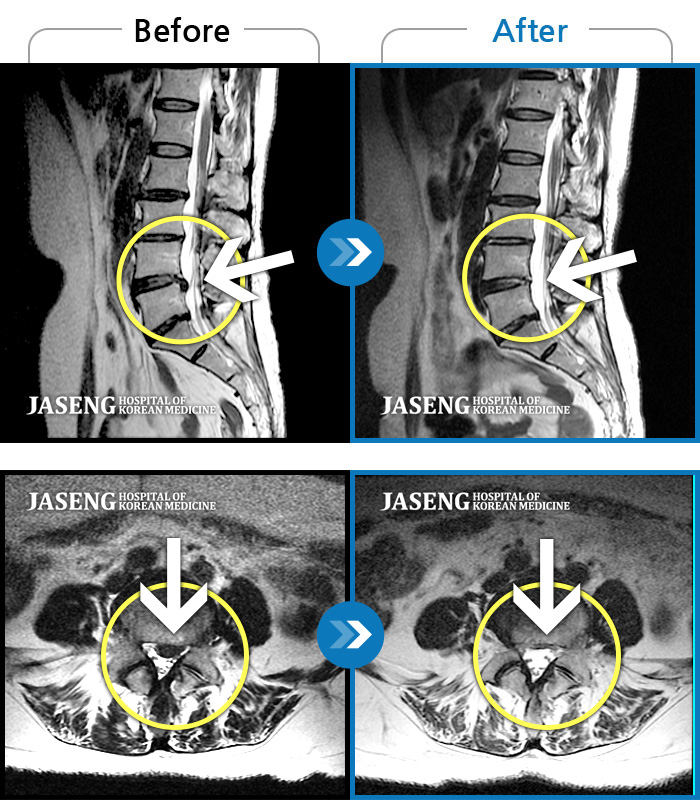

허리통증이 심해서 숙이기 어렵고 차에서 내리기 힘들었습니다.

2021.01.06 ~ 2025.03.10